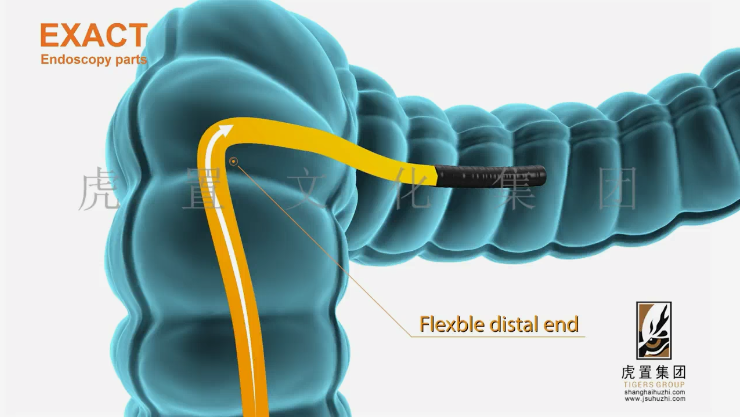

深耕于数字设计及展示领域的虎置文化集团成立20年,正努力成为全球知名的数字设计及展示服务商,为客户提供设计、展示及施工的一站式服务,为不同行业客户提供基于文化创意服务的整体解决方案。设计包括:建筑设计、景观设计、规划设计、展馆设计、室内设计、BIM设计;展示包括:三维动画、全息展示、影视广告、数字展馆、二维动漫、3D仿真效果图、VR&AR、企业宣传片等;施工包括:展馆展厅、室内装饰、幕墙工程、亮化工程。

公司依靠先进的三维动画制作技术,致力于三维动画的定制和制作,为数百家企业制作了各种类型的三维动画,有着丰富的实践经验和服务水平,制作的三维动画具有更灵活的表现形式、更强大的说服力和更生动的效果,成为众多企事业单位宣传产品、拓展市场、塑造品牌影响力的重要工具。服务政府、部队、世界五百强企业百余家;服务“一带一路”、“中国 制造2025”等重大国家战略项目;服务美国斯坦福、上海同济大学等国内外知名高校。